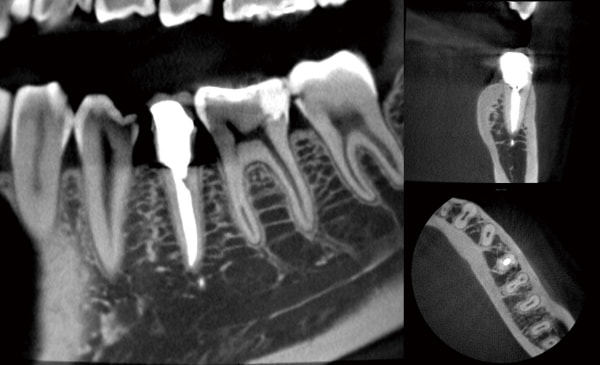

高精細なCT撮影を

最小ボクセルサイズ80μmでの高精細撮影 ※フリーモードで Φ40mm×H40mm 選択時

撮影範囲を予めプリセットした撮影モードに加え、撮影範囲を5mm単位で可変可能なフリーモードを搭載しています。

照射野を絞る事で、最小ボクセルサイズ80μmの高精細画像が取得できます。

ボクセルサイズとは?

ピクセルは、2D画像を構成する最小単位の正方形を意味するのに対して、ボクセルは3D画像における最小単位の立方体を意味します。

ボクセルサイズが小さいほど理論上、より高精細な画像になります。

最短6.7秒、通常12秒で高画質CT撮影を実現

短時間での撮影は、被曝量を抑えることにつながり、患者さんの負担を軽減することができます。

BEL-Xでは、すべての撮影モードで12秒、さらに高速モードでは6.7秒の短時間撮影が行え、患者さんが動く事で起こるアーチファクトの軽減が期待できます。

多様なFOVサイズに対応

数歯に限定した小さなサイズから、全顎と顎関節を含む大きなサイズまで、用途に合わせた多様なFOVサイズの撮影を行うことができます。

画素値を補正CT値として活かす

CT値が既知の基準ファントムを用いて補正を行います。CT画像で顎骨の形状や構造を見るだけでなく、任意領域のCT値を表示、またCT値を色付け表示することで顎骨の硬い・軟らかいを視覚的に確認することができます。